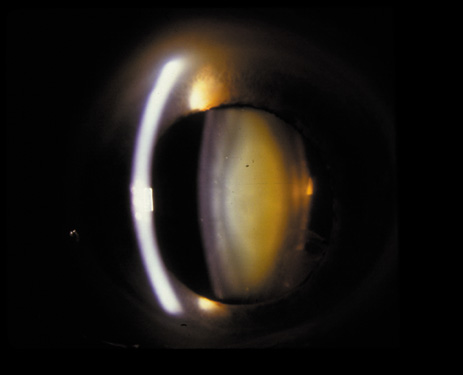

The PSC is the least prevalent subtype in most population-based studies.18 These cataracts often occur in combination with nuclear or cortical cataracts in the later stages. They are easily noticed on retroillumination because they are usually located centrally, and may interfere with funduscopy (Fig. 12). In early stages, patients usually complain of subjective symptoms such as glare disability32 and difficulty focusing on near objects. This is because when the pupil constricts during accommodation, the light entering the eye becomes concentrated centrally, where the PSC is also located. This causes light scattering and interferes with the ability of the eye to focus an image on the macula. In addition, these opacities lie at or near the nodal point of the eye, further interfering with focusing of the image on the macula.

Fig. 12. PSC. Note the central location, which gives rise to severe glare disability.

One can examine this type of cataract with direct illumination, using the narrow and broad beams of the slit-lamp to show the characteristic granular inner surface immediately in front of the posterior capsule (Fig. 13). The problem with this technique, however, is that patients may not tolerate any prolonged direct illumination because of the glare. Retroillumination is therefore more useful for revealing the outline of the opacity, since it is usually seen as an “island” in the center of the posterior capsule, which is further highlighted by the shadow cast by the opacities.33 However, in the early stages of this type of cataract, the dust-like particles that might be noticeable in the central posterior subcapsular area with direct illumination disappear or are difficult to see with retroillumination (Fig. 14). Eventually this “dusting” becomes dense enough to cast a shadow and thus appear on retroillumination. The smooth orange background of the fundus helps to highlight the rough, irregular pseudopodia-like edges of the central opacity. In advanced stages, the PSC may become a thick, calcified plaque (Fig. 15). During surgery, excessively vigorous scraping or vacuuming of the calcified opacity can lead to rupture of the posterior capsule. Usually, small remnants that are left behind after surgery are reabsorbed and do not interfere with vision; otherwise, they are easily treated with a neodymium : yttrium (Nd:YAG) aluminum garnet laser. Pathologic evidence suggests that most PSCs result from the migration of bow region cells into the potential space (along with accumulated cellular debris) between the posterior capsule and the cortex.34–36